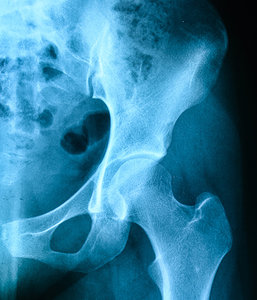

The strength of chiropractic physical rehabilitation is first and foremost CMT, closely followed by our appreciation of a whole-body approach to balancing the entire kinetic chain. Thoughtful rehabilitation of the low back goes beyond handing a patient a sheet of exercises, regardless of whether it is based on McGill's approach of neutral spine or the flexion model of Williams, Hodge or Cox. (These were all discussed in the first three articles in this series.) Now, it is time to look at the relationship of the hip (acetabular joint) and pelvis (sacrum and ilium) in low back syndromes.

Assessment and treatment of the hips and SIJ in all planes of motion is beyond the scope of this article. The SIJ is complex in its biomechanics, having an upper and lower component with the sacral base being able to rotate both anteriorly and posteriorly on the ilium – nutation and counternutation, respectively.

Dynamically, in the gait cycle the ilium rotates around a frontal horizontal axis on the non-weight-bearing side, while on the weight-bearing side the ilium rotates around a vertical axis. Repetitive load, trauma, degenerative changes or maladaptive compensatory gait patterns can result in sacroiliac dysfunction. In addition, acquired hyper- or hypomobility of the SIJ results in altered load transmission, which further impacts the lumbar spine.

O'Boyle's contends the hip is a stability region; therefore, it tends to require extra attention to maintain mobility. Joint play of the hip in flexion, extension, long-axis extension, and internal and external rotation all need to be evaluated. Assessment of the LPH soft tissues for flexibility, strength, and tone via examination and functional movement screens completes the diagnostic algorithm.